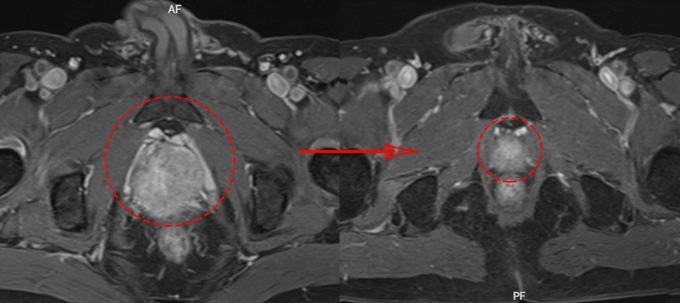

Kết quả xét nghiệm máu của ông Chuyên hai năm trước cho thấy nồng độ kháng nguyên đặc hiệu tuyến tiền liệt (PSA) ở mức 52,5 ng/mL, cao hơn 13 lần ngưỡng tối đa (4 ng/mL) ở nam giới khỏe mạnh. Chụp cộng hưởng từ MRI vùng chậu ghi nhận tuyến tiền liệt lớn, kích thước 43x39x44mm, tương đương 38 g.

Bác sĩ chỉ định sử dụng thuốc nội tiết tân bổ trợ gồm thuốc tiêm mỗi tháng một mũi và thuốc uống hàng ngày cho ông Chuyên. Sau một tháng, xét nghiệm máu cho thấy chỉ số PSA giảm về mức bình thường. 4 tháng sau, chụp MRI ghi nhận tuyến tiền liệt giảm kích thước đáng kể, từ 38 g còn 12 g, bệnh nhân hết khó tiểu. Tiếp đến, người bệnh được xạ trị gia tốc điều biến liều (IMRT) trong 37 buổi. Liều xạ được phân bổ theo kế hoạch, tập trung vào tuyến tiền liệt để tiêu diệt tế bào ung thư, giảm dần liều ra vùng ngoại vi để bảo vệ bàng quang, trực tràng và xương chậu, hạn chế tối đa tác dụng phụ.

Theo bác sĩ Sơn, tế bào ung thư tuyến tiền liệt dùng hormone sinh dục nam giới là testosterone như nguồn nhiên liệu để tăng trưởng. Liệu pháp nội tiết tân bổ trợ sử dụng các loại thuốc làm giảm hoặc chặn testosterone để cắt nguồn nhiên liệu, khiến ung thư ngừng phát triển, teo nhỏ. Cùng với xạ trị ngoài điều biến liều (IMRT), khối u của ông Chuyên giảm 70% kích thước chỉ sau 4 tháng, không cần phẫu thuật. Bệnh nhân tiếp tục điều trị nội tiết trong hai năm.